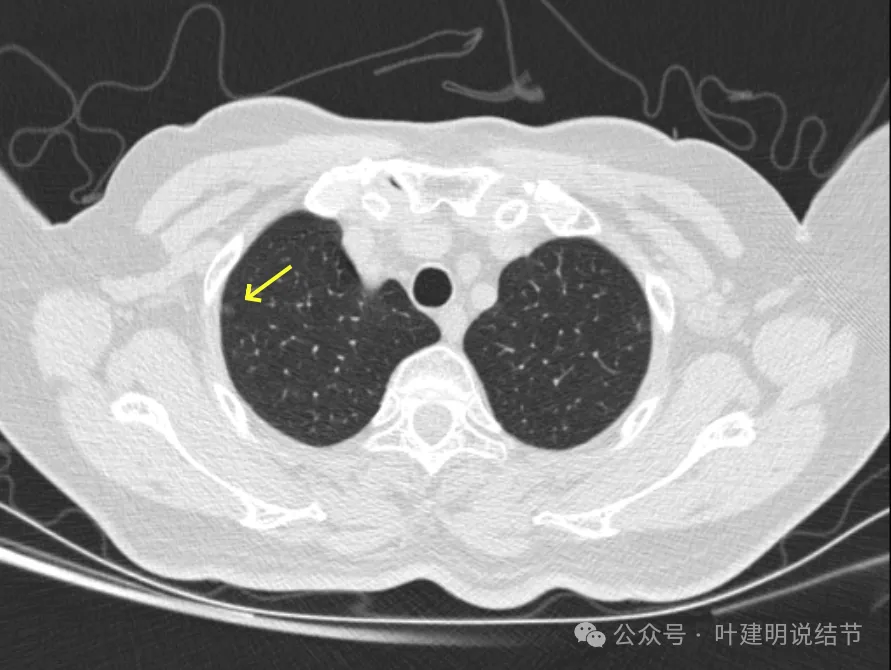

病灶21-22:两肺淡磨玻璃结节,轮廓较清。

病灶23-26:两肺微小淡磨玻璃结节,轮廓较清。